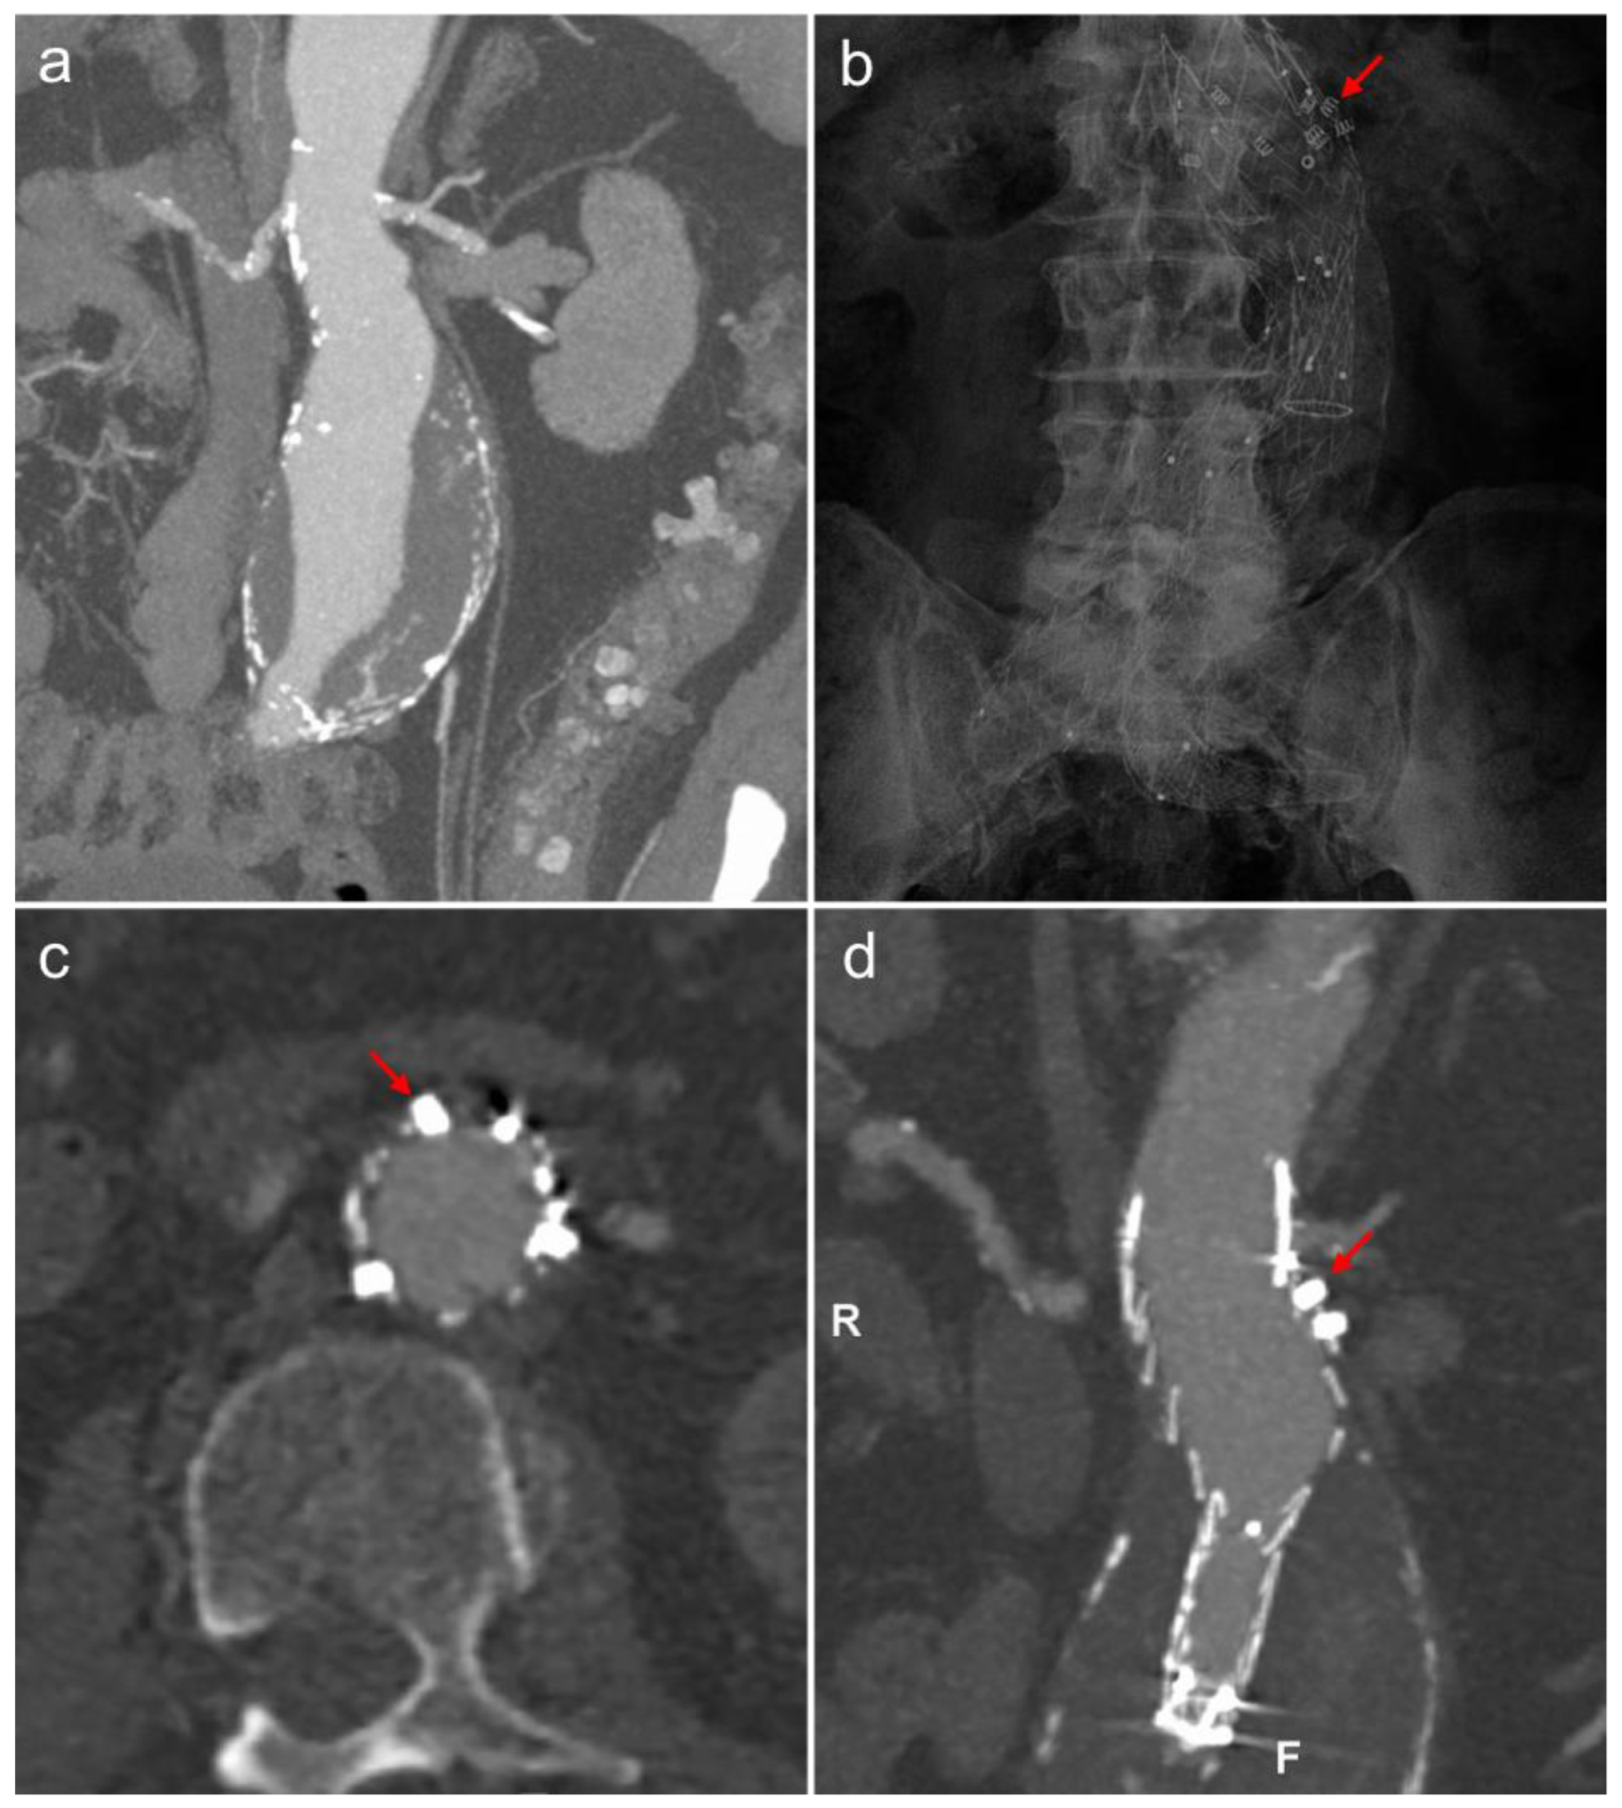

3.3. Endoanchors